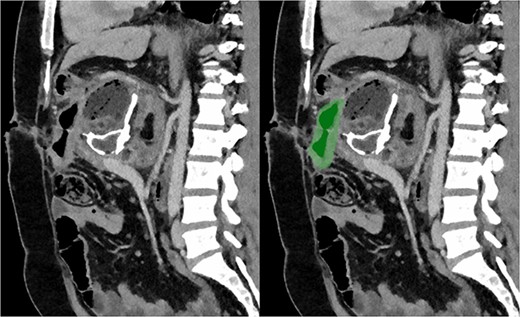

Sagittal section of post-operative CT with portal venous contrast demonstrating cystojejunustomy, highlighted in green, anastomosed to the origin of the fistula.